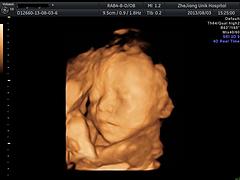

浙江优你可妇科医院场所环境雍容优雅,是从顾客的体验进行设计的,确保孕妇在此能够享受到舒适的环境。我们的营业时间是在周一至周日,提供的三维彩超可支持电话预约的方式进行预约。

伴随着快节奏的生活,健康养生娱乐休闲等相关方面问题越来越受到人们的重视。浙江优你可妇科门诊部有限公司创建于2009-05-18,坐落在浙江省杭州市拱墅区美都广场D座1-2楼,以提供优质的三维彩超服务为业务,致力满足孕妇的需求,获得了广大需求者的青睐。

我公司从事的三维彩超主要服务于杭州市地区,具有专业、尽责的特色,并且我们提供了到店服务的服务方式。质量,诚信务实是我们的服务根本,为了让孕妇更满意,我们将不断提升服务品质。

浙江优你可妇科门诊部有限公司把专业的理论知识和精湛的技术手法作为自己的核心竞争力和生命线,提供的三维彩超获得了广大孕妇的支持与信赖。三维彩超是以项目计费,为了能够更好的服务于大众,顾客可采用现结的方式付款。